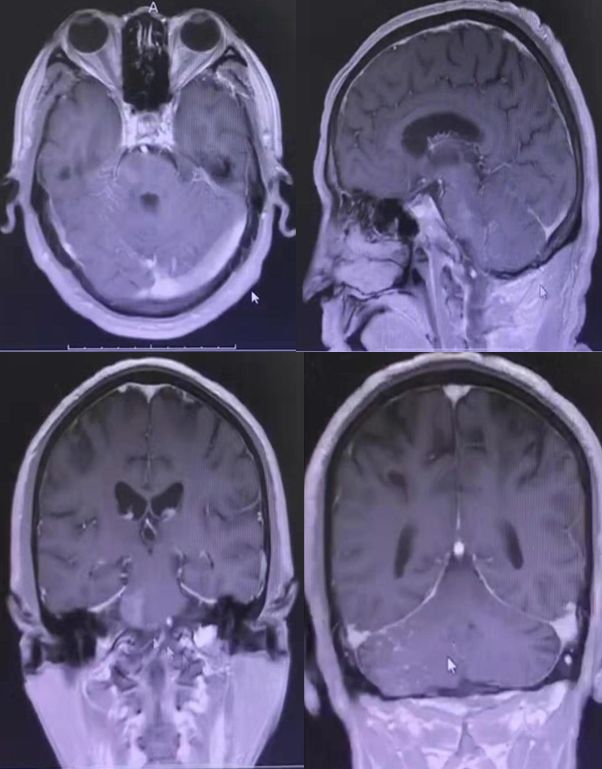

病例11

患者男性,54岁,左侧肢体乏力4月,右侧肢体乏力1月。

答案:弥漫性星型细胞瘤

该病一般为亚急性起病,进行性加重。若出现进行性加重的头痛、偏瘫和癫痫发作。影像学上显示脑实质内多个脑叶受累的病变。影像学检查示病变弥散,侵犯大脑半球2个或2个以上脑叶。CT平扫病灶可呈高密度、低密度或等密度,病变边界欠清楚,同一病例不同病灶密度也可不相同。病灶可强化或不强化,瘤周多有不同程度水肿。MRI扫描病变呈弥漫性斑片状。在T1上以低信号为主,在T2/FLAIR上呈均匀高信号,边界不清,病变区周围脑组织肿胀、脑沟变浅、变平、脑室变窄。占位效应不明显,中线结构无明显移位,周围正常脑组织结构仍可辨识,无囊变、钙化和肿块形成。增强扫描可呈多发不规则斑片状和大片状改变,也可无明显强化。